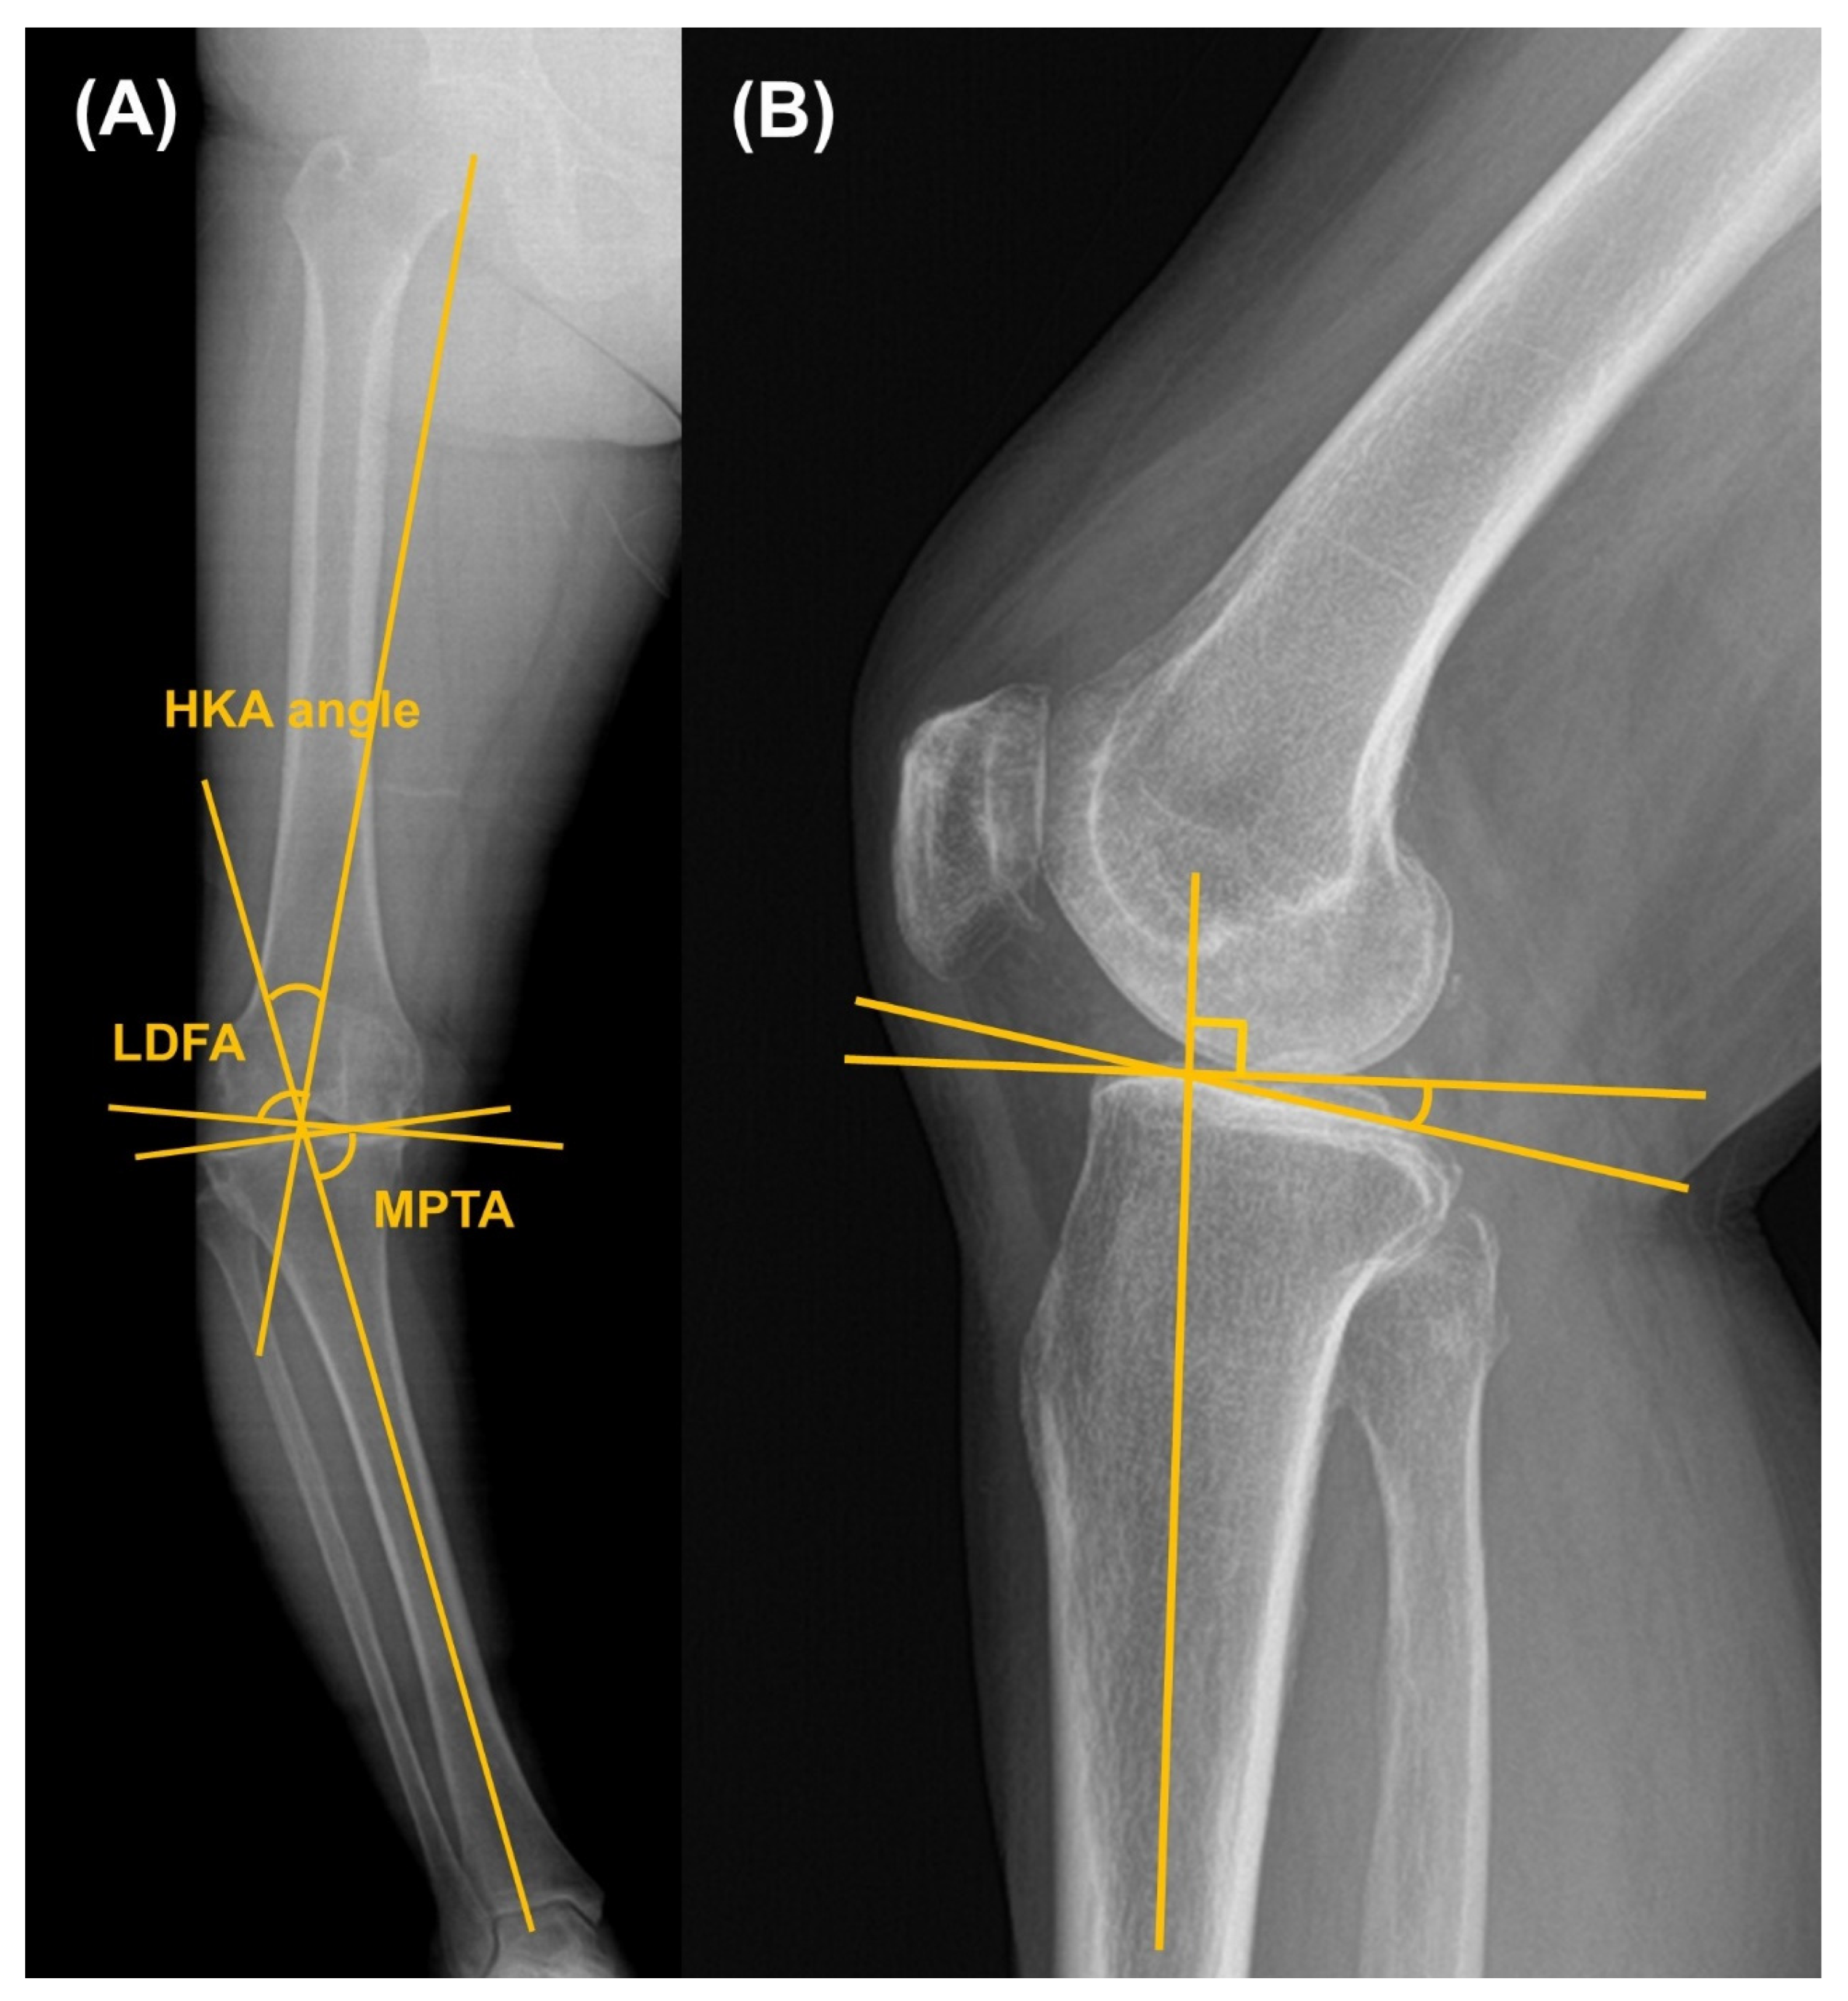

| HKA angle, ° | 17.0 ± 2.8 | 18.1 ± 3.9 | 0.007 |

| HKA angle, ° | 17.7 ± 2.9 | 18.1 ± 3.9 | 0.465 |

| LDFA, ° | 88.9 ± 2.5 | 88.6 ± 2.4 | 0.477 |

| MPTA, ° | 83.1 ± 2.8 | 82.3 ± 3.2 | 0.148 |

| HKA angle, ° | 1.8 ± 2.6 | 2.0 ± 2.9 | 0.701 |

| LDFA, ° | 89.6 ± 1.7 | 89.2 ± 1.3 | 0.501 |

| MPTA, ° | 89.3 ± 1.8 | 89.8 ± 1.6 | 0.063 |